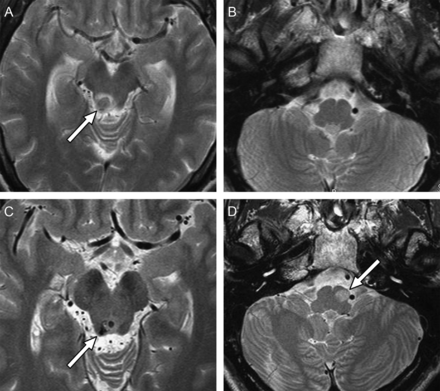

三个月后脑干出血,MRI显示hyperintense损伤左一个45岁的男人的下橄榄核(图)。患者完全无症状,但展出oculopalatal震颤(选择),有节奏的腭振荡,和小振幅垂直摆动的右眼眼球震颤,最佳可视化眼底检查(见视频)。

选择是由抑制性dentato-olivary路径的中断,导致同步振荡的橄榄形的神经元。这个途径穿过中脑然后下降到侧下橄榄核。1,2